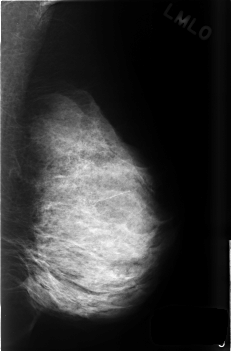

C_0501_1.LEFT_MLO

LEFT_MLO LINES 4560 PIXELS_PER_LINE 3000 BITS_PER_PIXEL 12 RESOLUTION 50 NON_OVERLAY